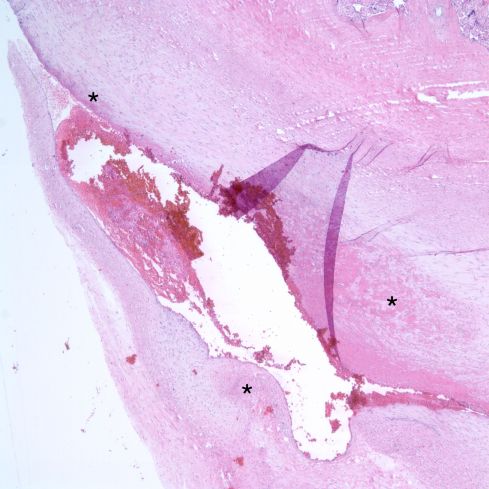

In 1973 Dr. DeSa published a paper “Intimal Cushions in Foetal Placental Veins” which was primarily concerned with observations on thrombi in veins on the placental surface[11]. The lesions described, including some in stem vessels, covered a variety of lesions. Those described as major intimal cushions likely were organizing thrombi. The end result of organization may be a small cellular scar protruding from the vascular intima (Fig 13)

Fig 13a: Mural fibrin thrombus showing various degrees of organization of fibrin (asterisks) in a oblique section of a surface chorionic vessel (H&E 4x)

Fig 13b: Higher power of mural fibrin showing ingrowth of pale scar, fibroblasts and macrophages between strands of fibrin (H&E, 20x)

Fig 13c: This longitudinal section of a surface chorionic vessel shows a well-formed intimal cushion presumed to be from an organized mural thrombus (arrow). This placenta showed occlusive thrombi in other sections. (H&E, 2x)